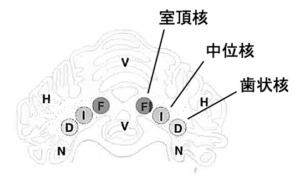

今回ご紹介するCecilia-Gabriella Danciuの報告では、1955〜1978年に発表された3つの論文が引用されていました。これら論文では動物実験(猫)を行い、小脳白質の深部にある3つの核※1のうち、中位核に障害を起こしたところ、以下の症状が現れたそうです。

※1 歯状核/中位核/室頂核 の3つ

中位核を栓状核/球状核に分けて4つに分類する場合もある

・同側散瞳

・同側PLR不完全

・同側眼瞼裂の拡大、対側第三眼瞼突出

この結果から、小脳中位核はなんらかの形で瞳孔支配に関与していることが示唆されました。

〈画像出典:Andre Jaggy/Simon R. Platt 監訳者:長谷川大輔 図解 小動物神経病学 2011年 株式会社インターズー より〉

これを踏まえて、今回ご紹介の2症例を振り返りましょう。

2症例とも小脳病変は小脳中位核が含まれており、過去の実験症例で確認されていた場所と一致。